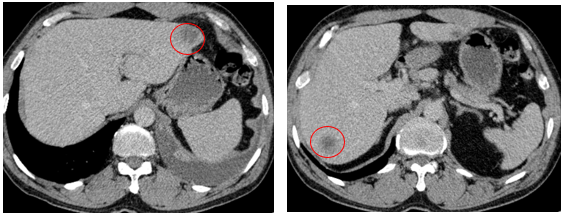

-         Chụp cắt lớp vi tính ổ bụng (08/2025): Nhu mô gan phải có vài nốt, nốt lớn nhất hạ phân thùy VII có nốt giảm tỷ trọng, ngấm thuốc kém sau tiêm đường kính 24mm, hạ phân thùy II, III có nốt 2 giảm tỷ trọng đường kính 13mm và 27mm. Các ổ đặc xương rải rác đốt sống ngực thắt lưng, xương cùng và xương chậu hai bên – theo dõi tổn thương thứ phát

Hình 04: Nhu mô gan phải có vài nốt, nốt lớn nhất hạ phân thùy VII có nốt giảm tỷ trọng, ngấm thuốc kém sau tiêm đường kính 24mm, hạ phân thùy II, III có nốt 2 giảm tỷ trọng đường kính 13mm và 27mm

-         Chụp cắt lớp vi tính ổ bụng (11/2025): Nhu mô gan phải có vài nốt, nốt lớn nhất hạ phân thùy VII có nốt giảm tỷ trọng, ngấm thuốc kém sau tiêm đường kính 8mm, hạ phân thùy II, III có nốt giảm tỷ trọng đường kính (tổn thương giảm đáng kể so với phim chụp ngày 08/2025). Các ổ đặc xương rải rác đốt sống ngực thắt lưng, xương cùng và xương chậu hai bên.

Hình 11: Tổn thương ngấm thuốc kém nhu mô gan hạ phân thùy II giảm đáng kể kích thước

Hình 12: Tổn thương ngấm thuốc kém nhu mô gan hạ phân thùy VII giảm đáng kể kích thước

+      Các tổn thương ngấm thuốc kém do di căn tại gan giảm kích thước đáng kể (27mm còn 8mm)